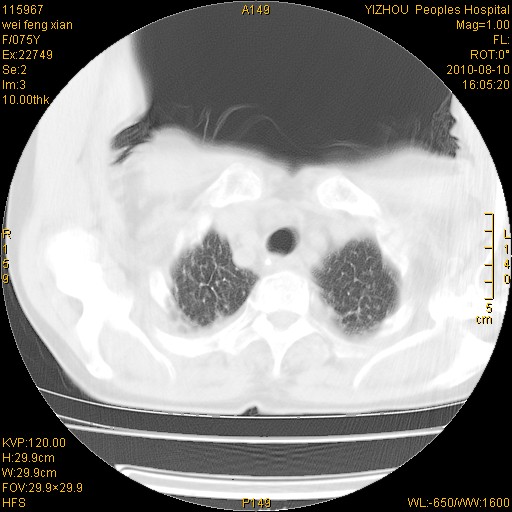

标题: CT28313:两肺弥漫性病变 [打印本页]

标题: CT28313:两肺弥漫性病变

女,75岁,患者反复头昏乏力面色苍白3年,再发10天入院。临床贫血查因。

双肺间质增生并右肺上叶炎性改变,不除外右肺上叶结核病肺内播散

考虑慢支伴右上肺慢性感染可能性大,建议结合临床排外尘肺可能。

考虑尘肺可能性大.

考虑右肺上叶炎症合并双肺结核可能性大,建议上传纵隔窗ct图片。

双肺结核可能性大

考虑尘肺并结核;右上肺支气管扩张!

结核、尘肺、支气管肺泡癌都不能除外

右肺上叶继发性肺结核伴肺内血型播散!

考虑右肺上叶继发性肺结核伴两肺播散。